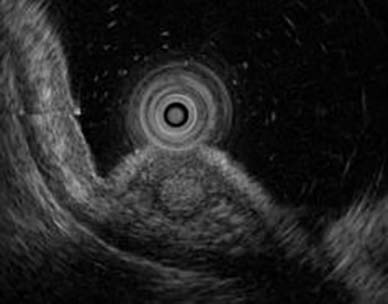

42歳女性。既往歴に特記すべき事項はなく、喫煙歴およびPPI使用歴もない。母方の叔父に胃ポリポーシスの既往がある。自身も胃ポリポーシスを指摘され、精査目的で当院を受診した。

上部消化管内視鏡検査では、胃体部に無数のポリープを認めた。また、体部大弯に15mm大の白色調領域(黄色矢頭)を認めた。生検の結果、ポリープは胃底腺ポリープ、白色部位はtub1であった。十二指腸および大腸にはポリープを認めず、血清ピロリ抗体も陰性であった。

GAPPS(gastric adenocarcinoma and proximal polyposis of the stomach)が疑われたため、遺伝カウンセリングを行った上で遺伝子検査を施行した。その結果、APC遺伝子のexon1Bに病的バリアントが検出され、GAPPSと確定診断された。

本疾患は、常染色体優性遺伝形式をとり、胃近位部に多数の胃底腺ポリープを形成する稀な疾患であり、これらのポリープは腺腫や腺癌への進展をきたすことがある。また、FAP(家族性大腸腺腫症)と異なり、十二指腸および大腸に多発する腺腫を認めないことが特徴である。

本症例では胃癌に対してESDが行われたが、GAPPSは新たな多発胃癌のリスクがあるため、根治治療として胃全摘が推奨される。患者の希望により胃全摘は実施されず、現在は定期的な内視鏡フォローアップを継続している。(New England Journal of Medicine に本症例が掲載されました!Tanaka K, Hirasawa T. Gastric Adenocarcinoma and Proximal Polyposis of the Stomach. N Engl J Med. 2025 Mar 13;392(11):e29.)